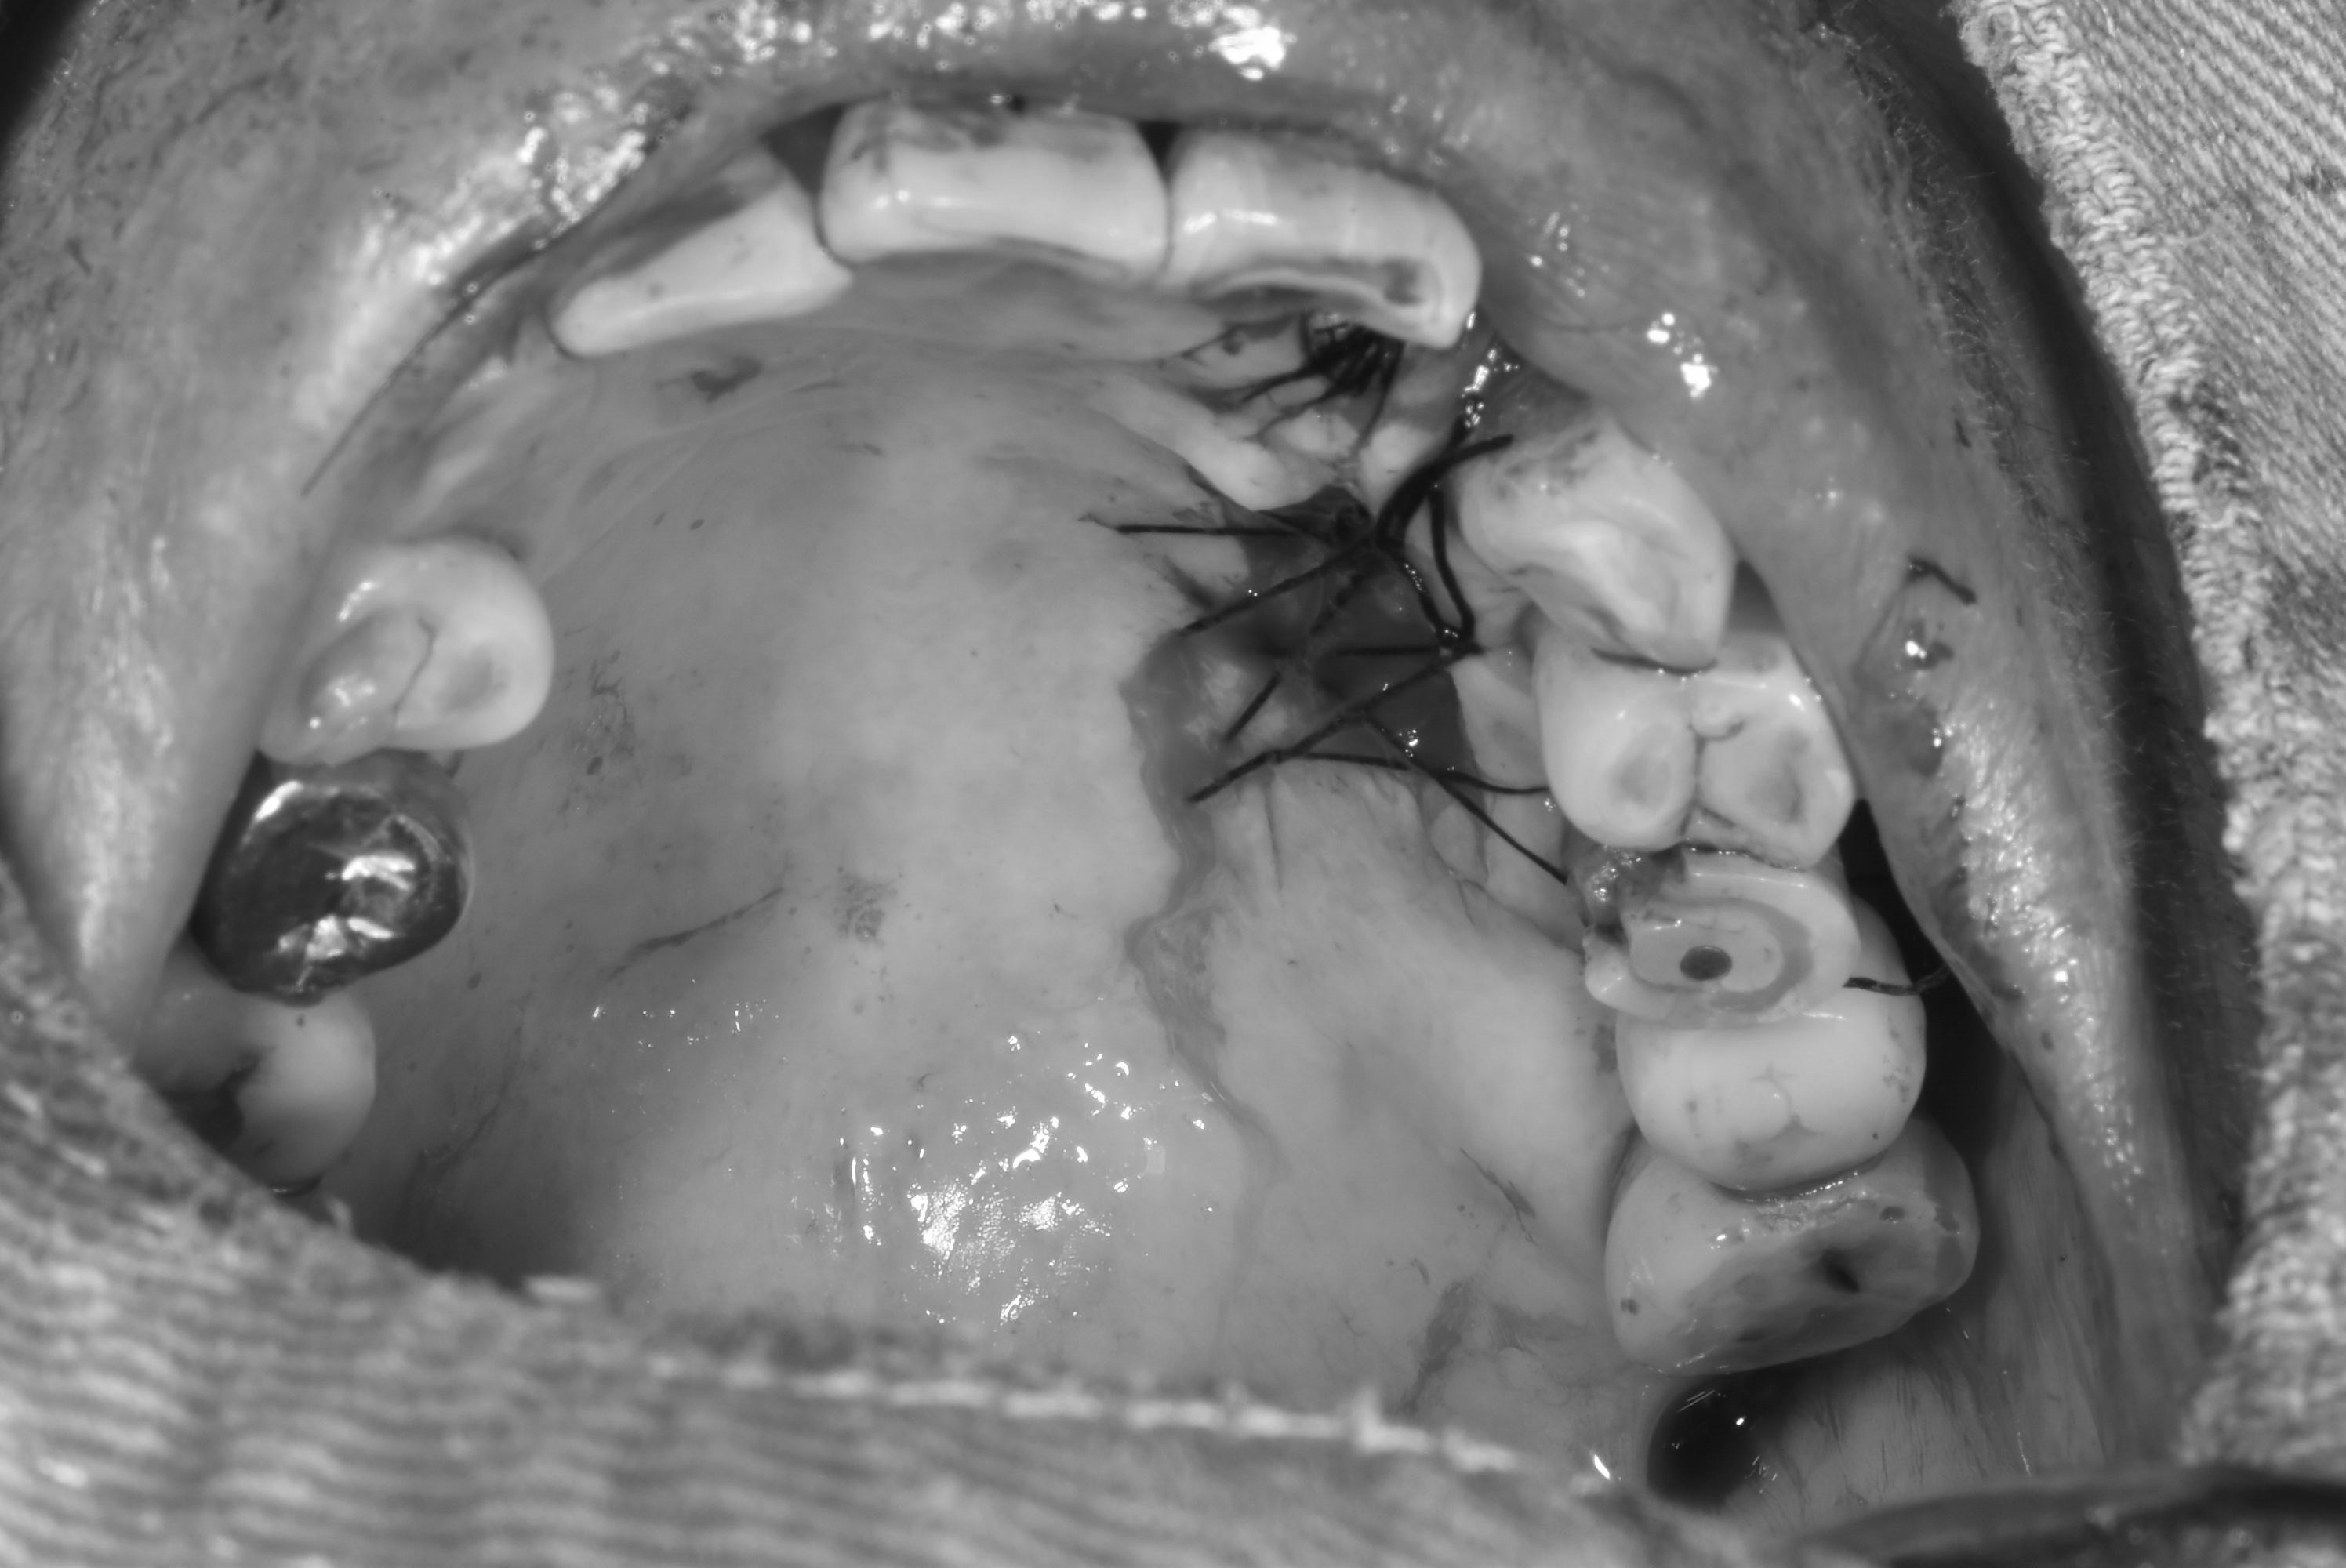

牙齦移植術(補肉)

手術案例

術前加術後案例

案例三